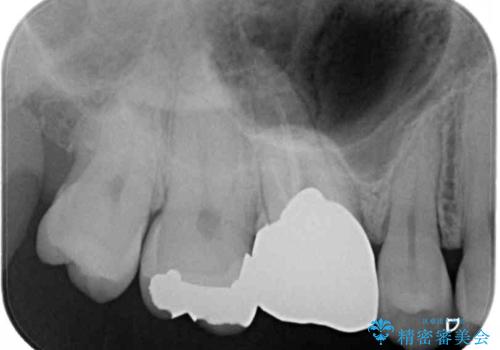

- 奥歯にものが挟まって痛みがあるとのことで来院された患者様です。

目視でも分かるくらいの欠損があり、歯の内部にむし歯が進行している状態でした。

上顎奥歯で目立たないことから、ゴールドインレー(PGAインレー)による修復治療をおこなうこととしました。